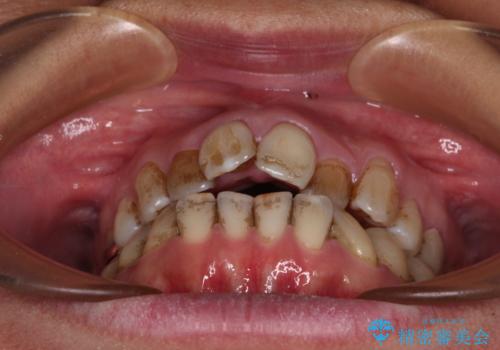

前歯の後戻り インビザラインでの再矯正治療

- かつて抜歯矯正を行ったものの、後戻りをしてしまったとのことで来院された患者様です。

上顎前歯が前突し、隣の歯が裏側に移動してきている状態でした。

飲み込みの状態を確認したところ、舌の突出癖が認められたため、それによる後戻りの可能性が高いと考え、舌のトレーニングを指導しました。

舌のトレーニングをしっかりと行ってくださり、10ヶ月で希望通りの歯列となりました。

日頃から飲まれる飲み物の影響で着色しやすいため、来院の度に着色除去のクリーニングも行っていました。